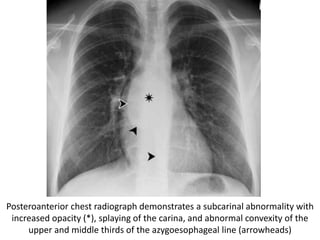

Posteroanterior chest radiograph demonstrates a subcarinal abnormality with

increased opacity (*), splaying of the carina, and abnormal convexity of the

upper and middle thirds of the azygoesophageal line (arrowheads)

Corresponding CT scan helps confirm a subcarinal mass (arrow),

which proved to be a bronchogenic cyst.